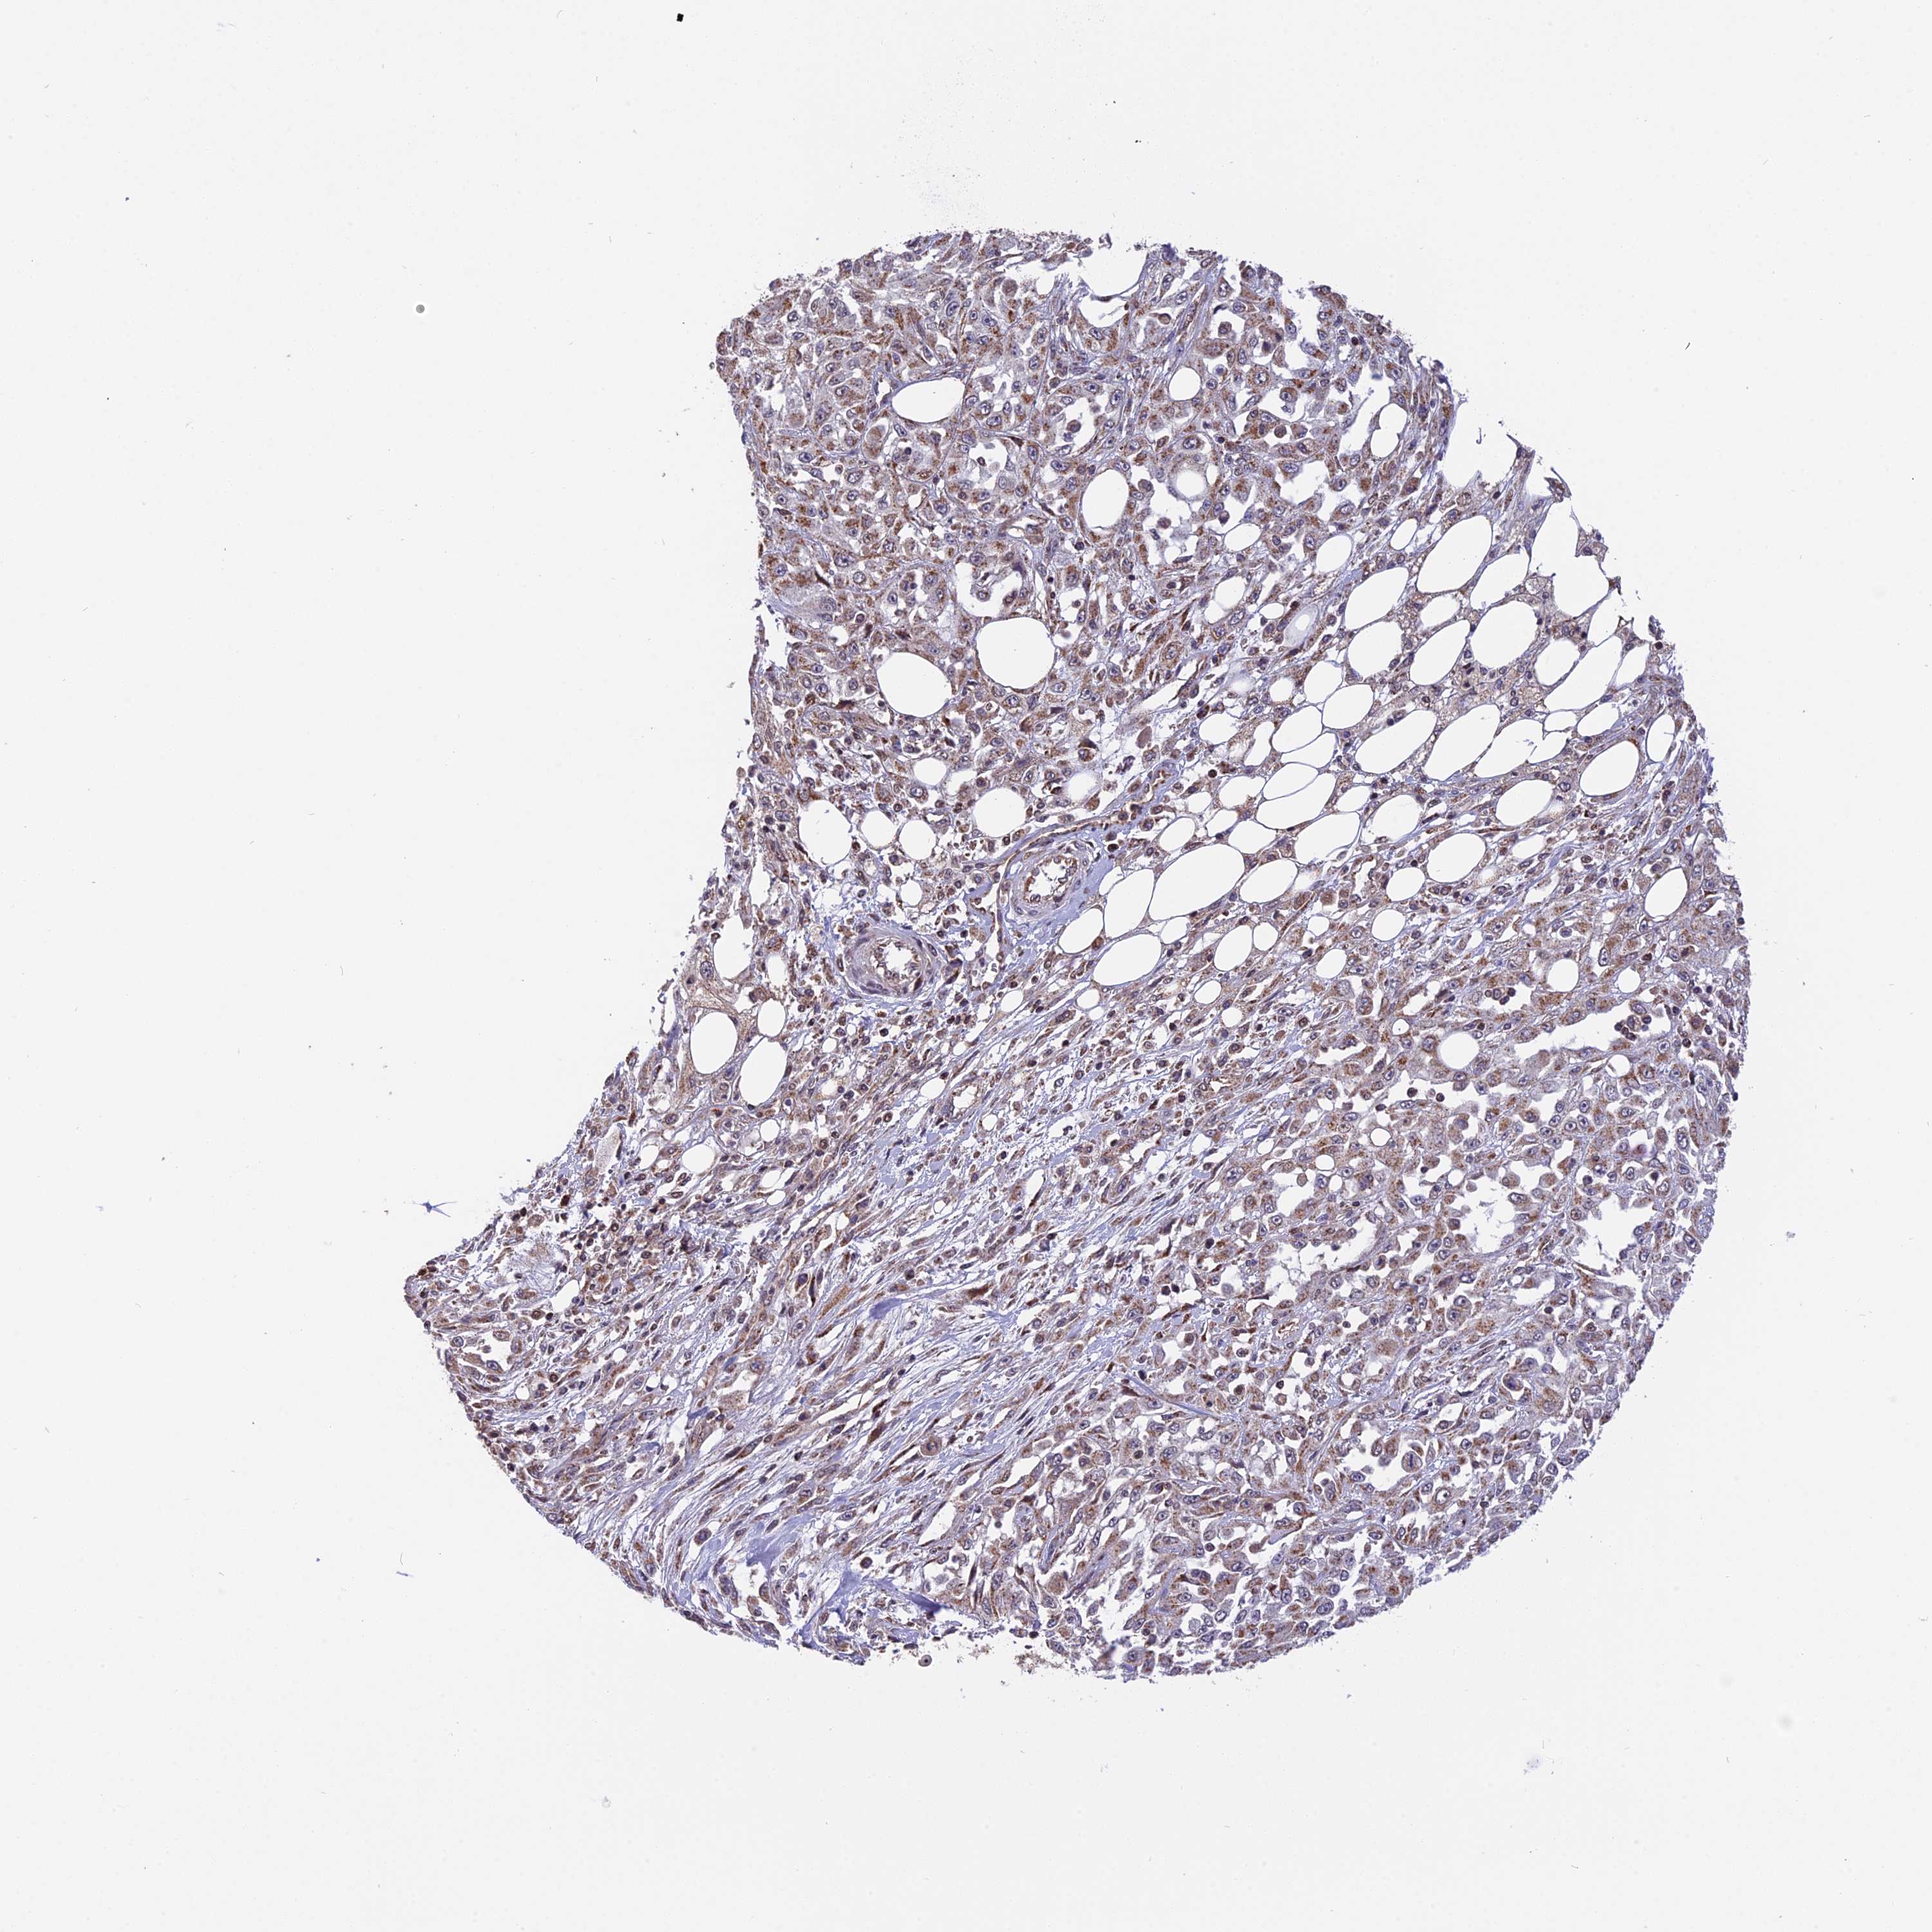

SKIN CANCER - Protein expressioni

A mouse-over function shows sample information and annotation data. Click on an image to view it in a full screen mode. Samples can be filtered based on level of antibody staining by selecting one or several of the following categories: high, medium, low and not detected. The assay and annotation is described here.

Antibody stainingi

Antibody staining in the annotated cell types in the current human tissue is reported as not detected, low, medium, or high, based on conventional immunohistochemistry profiling in selected tissues. This score is based on the combination of the staining intensity and fraction of stained cells.

Each image is clickable and will lead to virtual microscopy that enables deeper exploration of all samples and also displays staining intensity scores, fraction scores and subcellular localization as well as patient and tissue information for each sample.

Antibody HPA041740

Staining

High

Medium

Low

Not detected

Intensity

Strong

Moderate

Weak

Negative

Quantity

>75%

75%-25%

<25%

None

Location

Nuclear

Cytoplasmic/membranous

Cytoplasmic/membranous,nuclear

Squamous cell carcinoma, NOS

Squamous cell carcinoma, metastatic, NOS